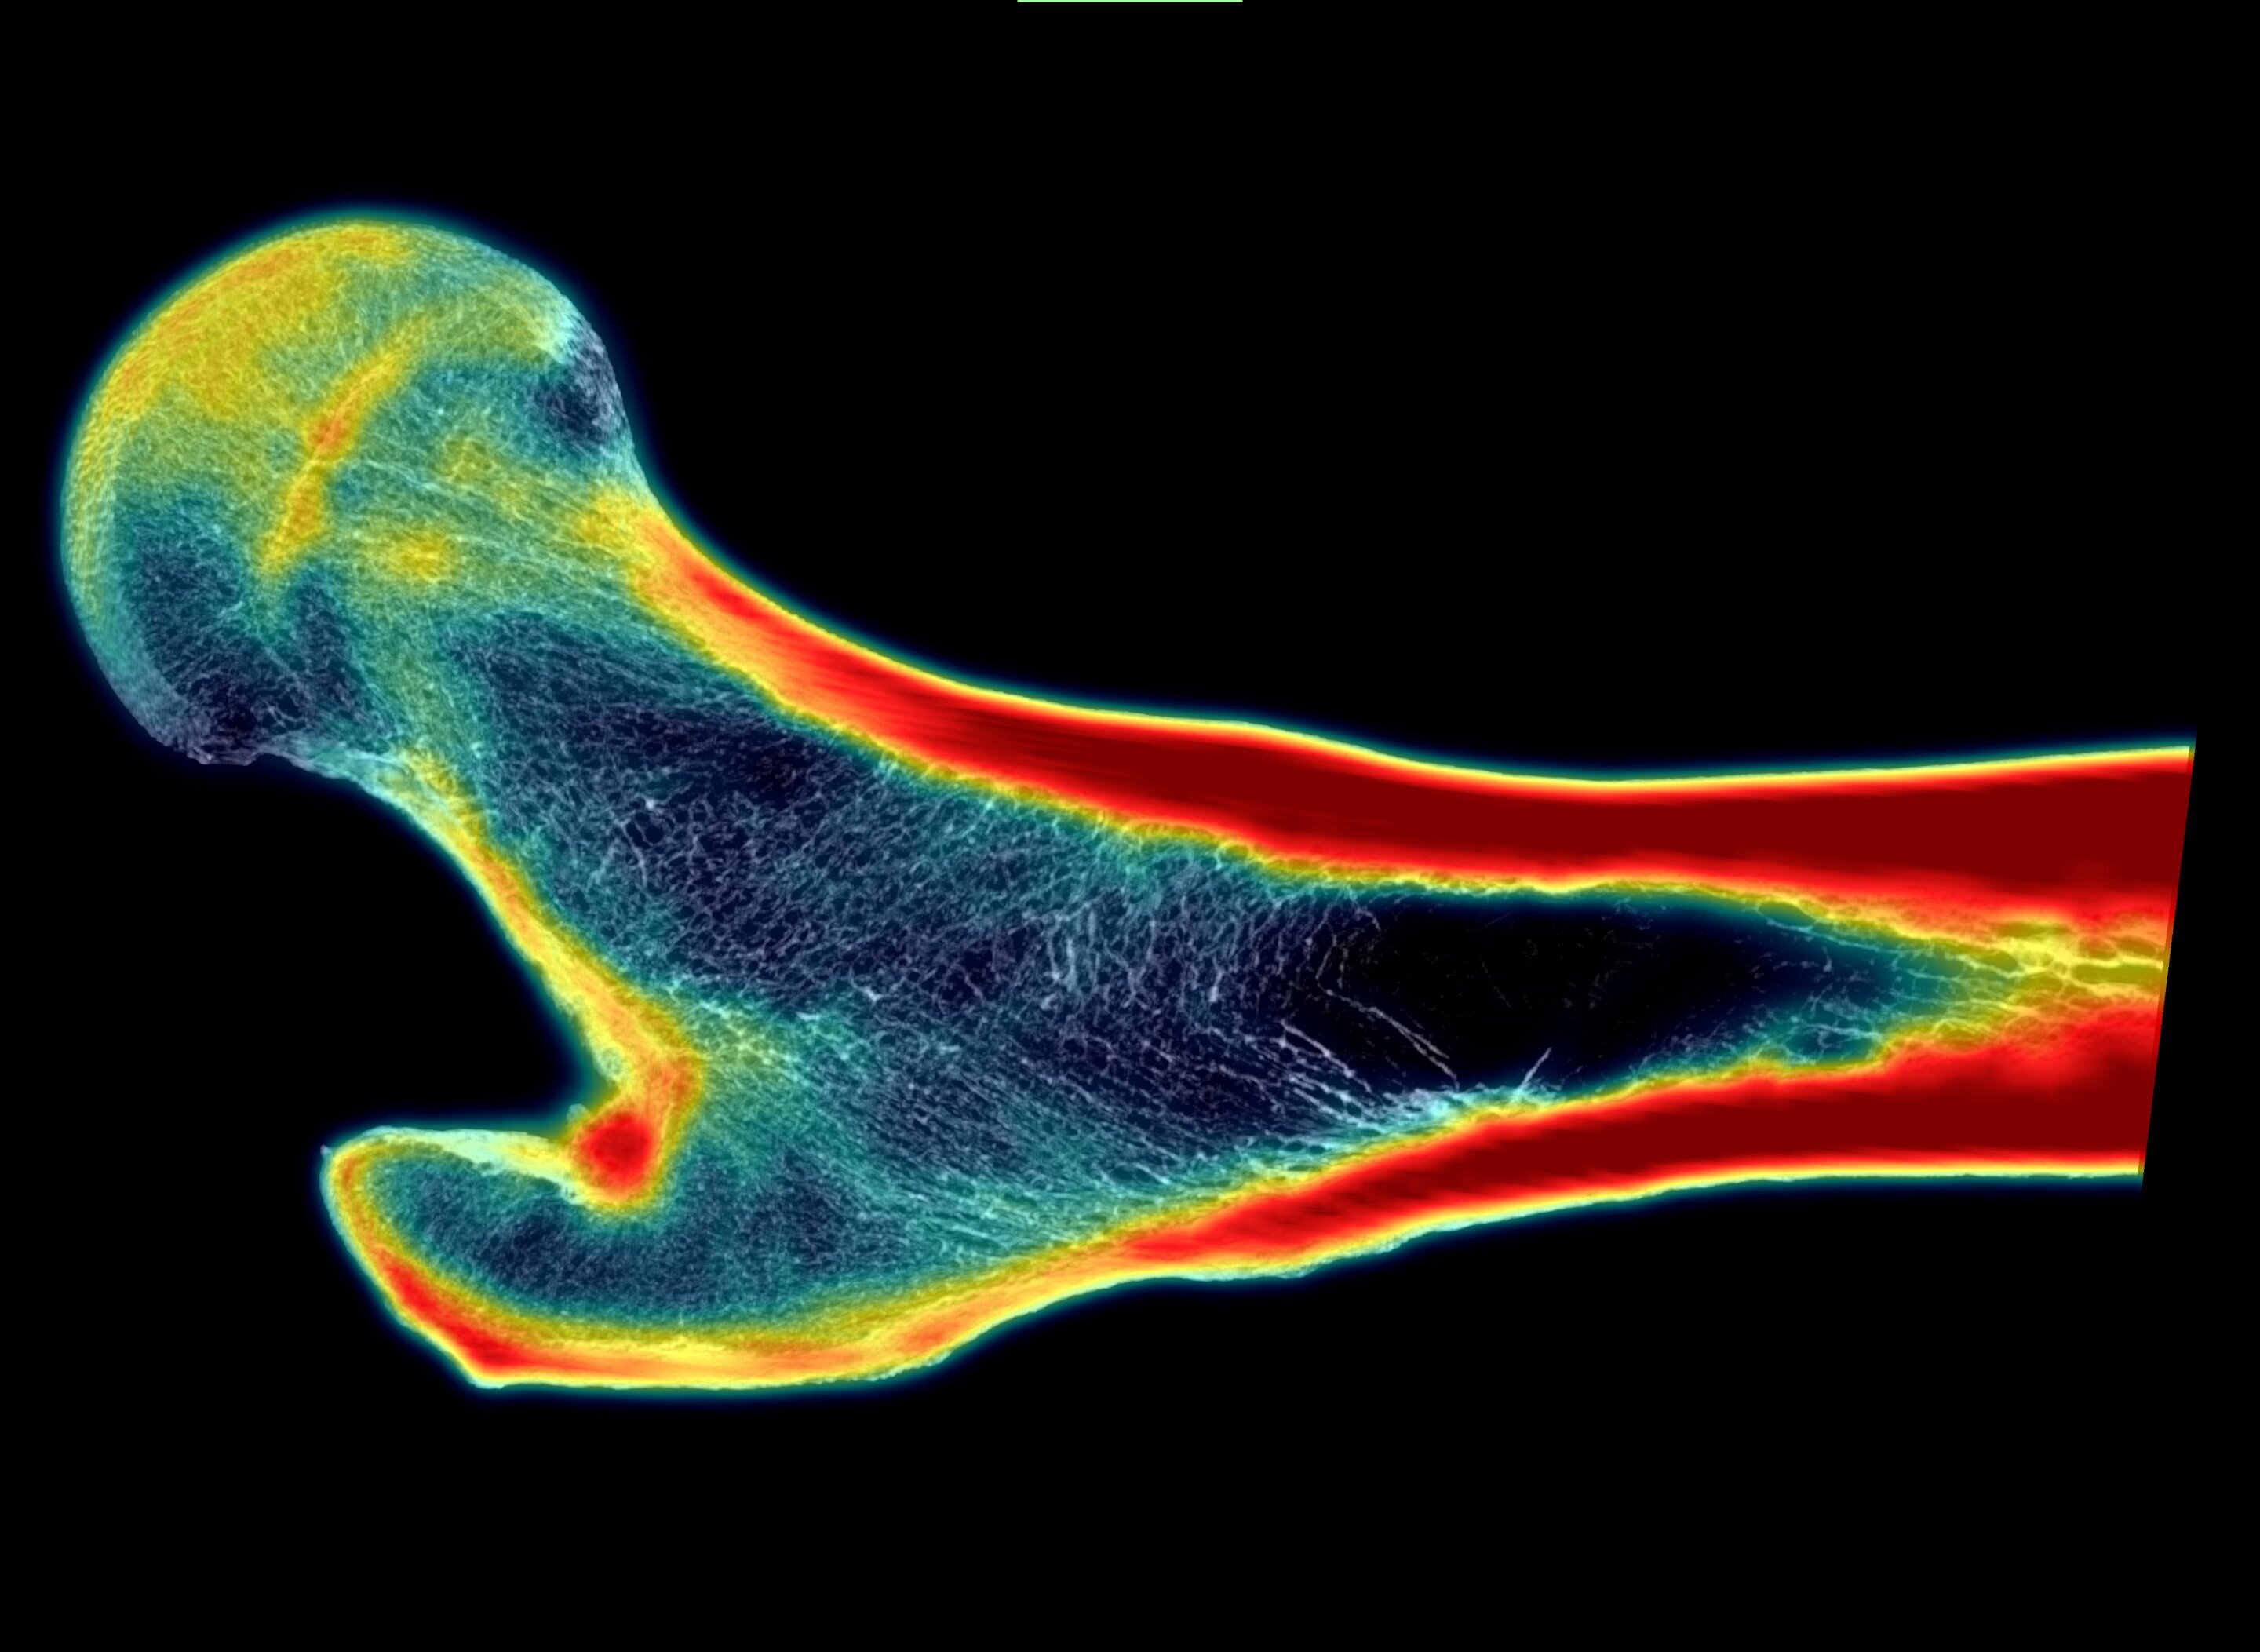

Ученые из Юго-западного исследовательского института (SwRI) разработали новую технологию, которая может значительно улучшить диагностику остеопороза и снизить риск переломов у пожилых людей. Метод основан на искусственном интеллекте (ИИ) и позволяет создавать изображения костей в высоком разрешении, которые детально показывают их внутреннюю структуру. Это помогает врачам точнее оценивать прочность костей и выявлять пациентов с высоким риском переломов.

В новом подходе используется глубинное обучение, которое обучает нейросеть восстанавливать высококачественные изображения из стандартных снимков. Это позволяет моделировать структуру кости и прогнозировать её прочность.